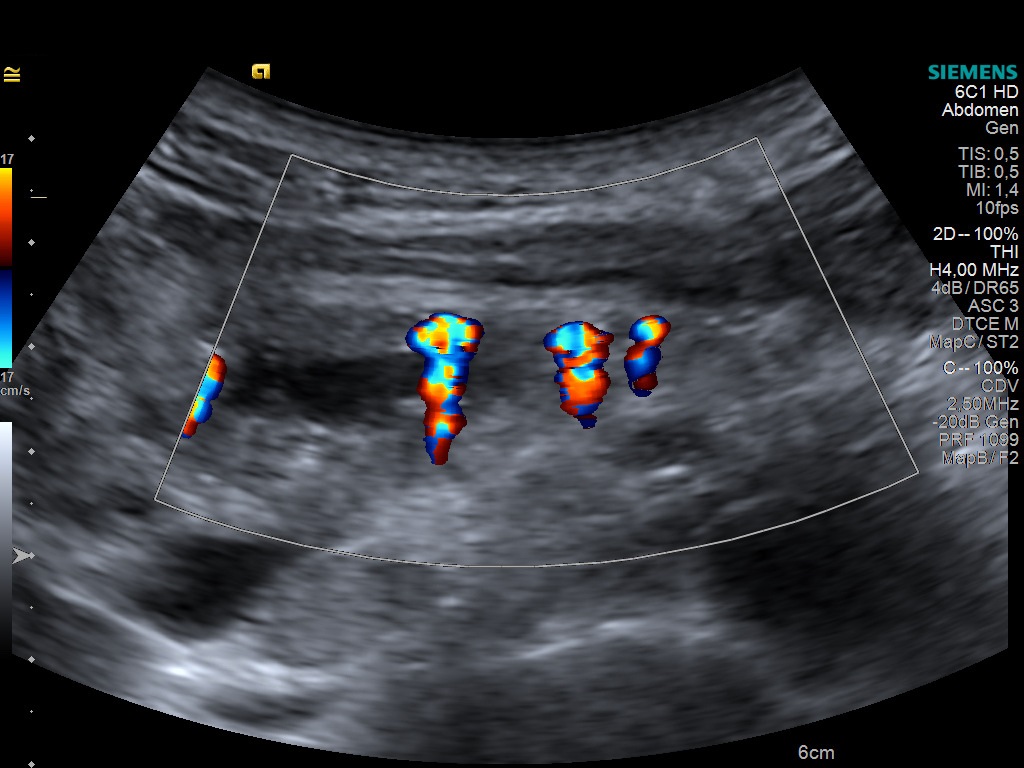

Student Image Challenge 71October 30, 2020EPSC Bylaw (9)November 3, 2020 Student Image Challenge 72 Student Image Challenge #72 1 / 1 Student Image Challenge #72 What is the name of the color Doppler artifact that can be observed in this case, a chronic pancreatitis with parenchymal calcification? Color bruit artifact Aliasing phenomenon Twinkling artifact Mirror image artifact Side lobe artifact Incorrect ....Please see the correct answer highlighted Correct! Twinkling artifact Your score isThe average score is 50% LinkedIn Facebook VKontakte 0% Restart quiz Case courtesy of Prof Adrian Săftoiu EFSUMBAdmin Related postsStudent Image Challenge 112Read more Comments are closed.